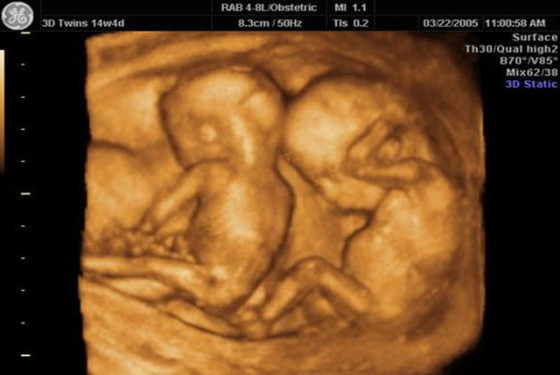

关于怀孕双胞胎三个月肚子有多大,我们可以通过怀孕双胞胎三个月胎儿图去了解,从中我们可以很清晰的看到怀孕三个月胎儿的发育情况。在怀孕三个月的时候,本来安静成长的胎宝宝会变得十分兴奋。准妈妈也会出现各种妊娠反应,有的准妈妈会有强烈的妊娠反应。

三个月的胎儿头部几乎占全长的一半,头发开始出现,五官也逐渐形成,两只眼睛还是相距比较远,下颌和两颊也开始发育。胎儿躯干伸直,尾巴完全消失。上,下肢也已从胎体伸出,并逐渐形成四肢,下肢很短,上肢达到最后的相对长度,指趾分化清楚,并有指甲出现。

四肢开始有活动。胎儿对刺激开始有反应,如眨眼,吸手指,手指脚趾张开等。宝宝在羊水中可以自由活动,有时下肢伸开,做出走的样子,有时又做出蛙泳的样子。但胎儿这时动作轻微,妈妈常感觉不到胎动。但准妈妈您请放心,您腹中的宝宝已经从一个胚胎成长为一个健康活泼的胎儿。